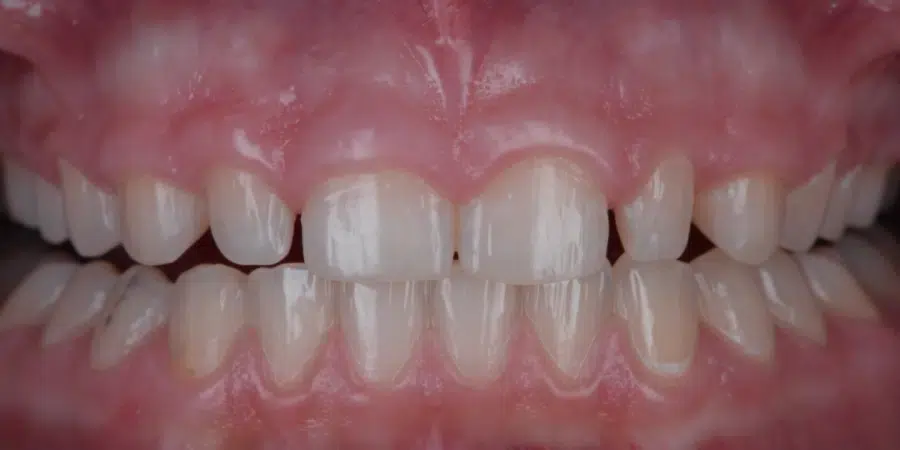

După